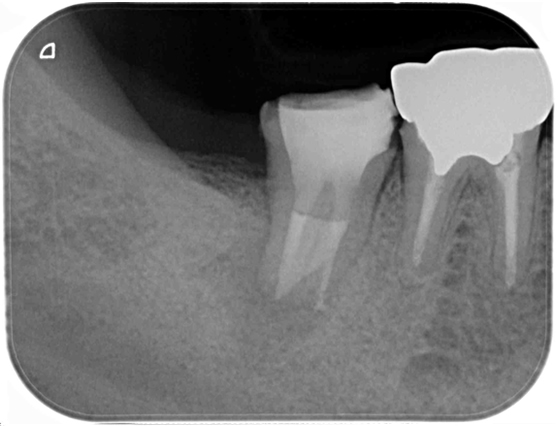

根管治療 症例8

治療後

治療に伴うリスク

根管治療することにより治療の影響で一時的に痛みが強くなることがあります。